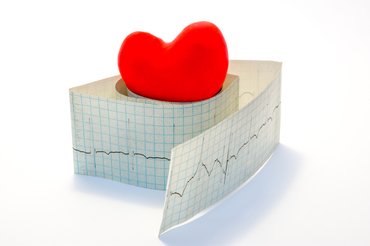

Erős szívdobogás: mikor normális és mikor jelez szívritmuszavart?

2026. 01. 18. 09:57